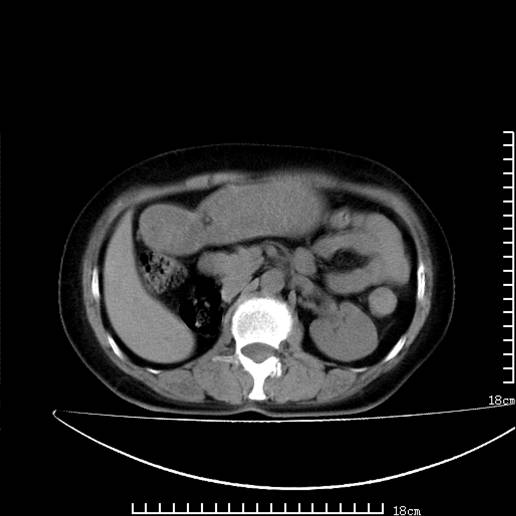

以下是引用pujunzhi在2008-5-30 15:31:00的发言:[br]异位肾—盆腔肾。当看到肾窝无肾脏时,要想到孤立肾和异位肾,异位肾最常见是盆腔肾,偶见胸腔,易误认为肺占位,只要想到就不会漏诊。建议增强扫描。